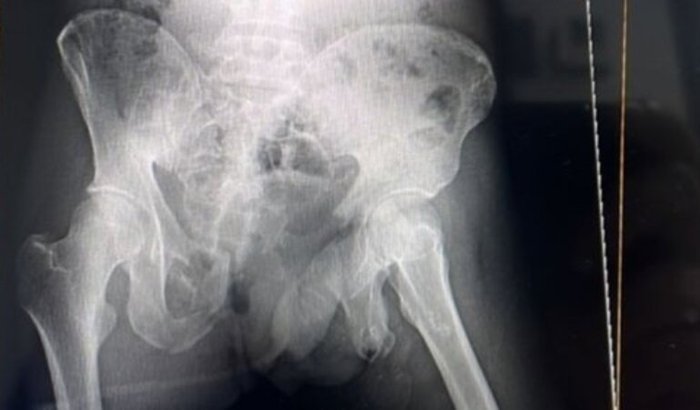

Em junho de 2025, o filho dela sofreu um gravíssimo acidente de moto. Ele ficou em coma na UTI, com múltiplas fraturas na bacia, conforme evidenciado na radiografia. Além disso, passou por uma colostomia e teve uma laceração de grau 3 na bexiga e na região pélvica.